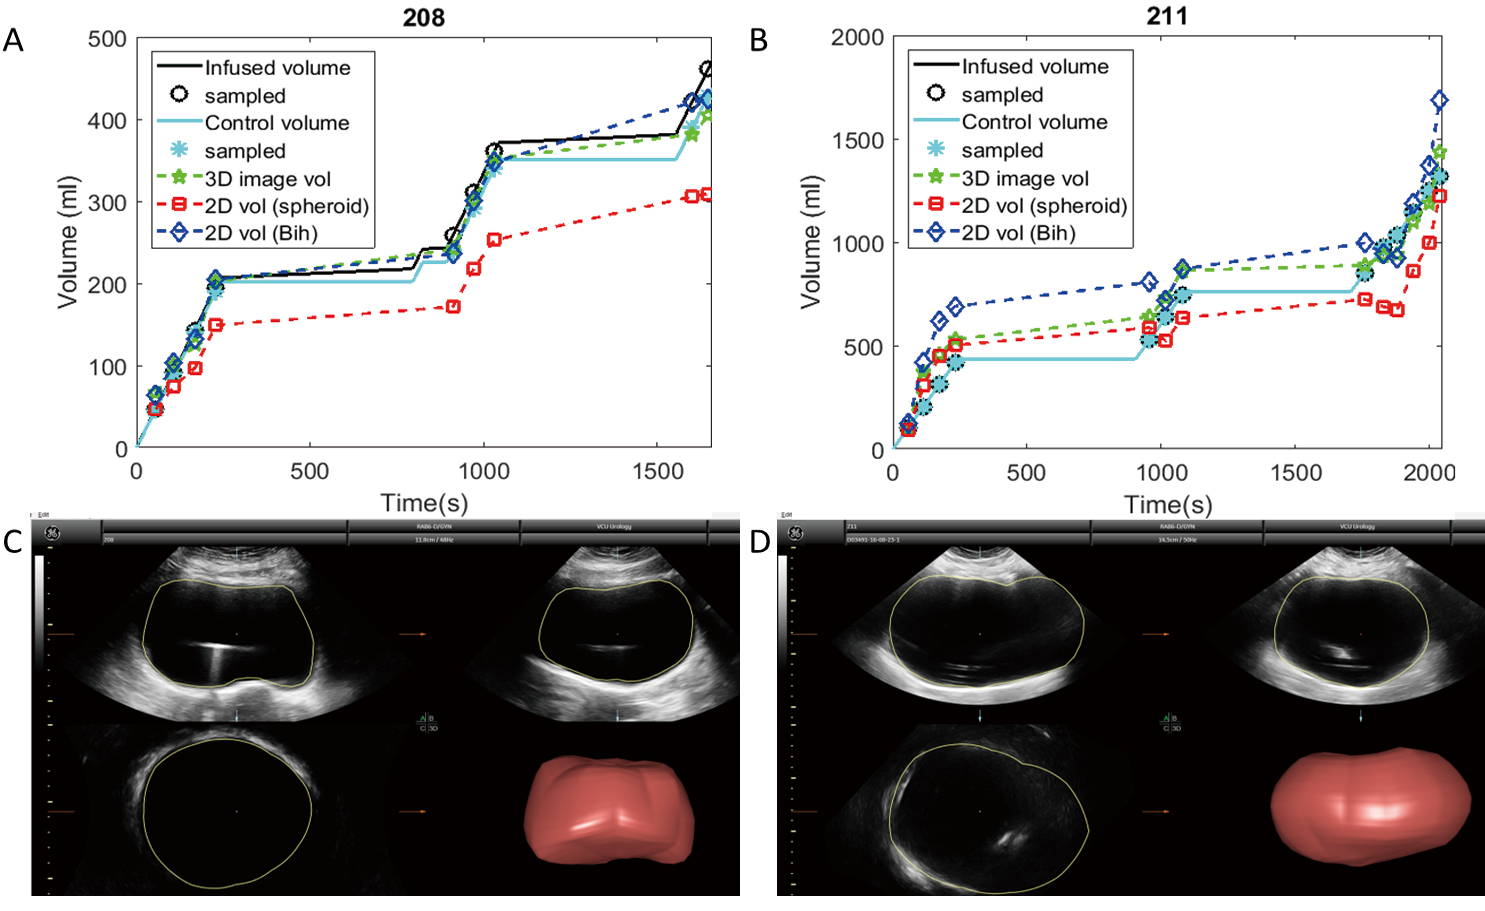

Results: Based on linear regression analysis, both Vbih and V3D were fairly accurate estimators of Vcontrol, but V3D was more precise. Vspheroid significantly underestimated Vcontrol.

Conclusions: Although the Vbih and V3D methods were more accurate than the more-commonly used Vspheroid method for measuring bladder volumes during UD, the V3D method was the most precise and could best account for non-uniform bladder geometries. Therefore, the V3D method may represent the best tool required for the continued development of non-invasive methods to diagnose OAB and other forms of voiding dysfunction.